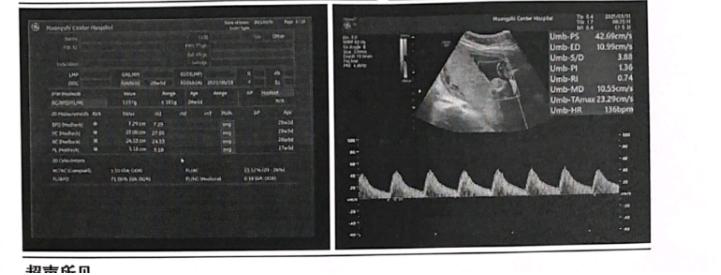

患者自怀孕以来,谨慎、饮食、睡眠可,大小便无异常,体重随孕周逐渐增加。对患者进行查体检查以及,未见明显异常,专科检查宫高脐上2指。单胎中期系统胎儿超声检查(产科)提示孕周:22周+6天超声孕周:23周+1天单胎,BPD:5.8mm;HC:21.2cm;AC:18.2cm;FL:4.0cm估计胎重:553g左、右侧脑室后角分别宽0.5cm、0.5cm,小脑横径2.4cm,小脑延髓池深0.5cm。胎盘:后壁厚:3.3cm;0级羊水平段:4.8cm;脐血流S/D:3.75胎心率:154bpm。阴道超声筛查:孕妇宫颈长约为3.2cm。

根据患者自述症状,病史,以及胎儿超声,阴道超声筛查结果等,我将患者诊断为孕1产0孕28+4周先兆流产。明确诊断之后,为患者办理住院手续,完善相关辅助检查。患者住院期间,给予硫酸镁、黄体酮保胎、补液等对症支持治疗。经过四天的对症治疗之后,患者情况好转,要求出院,评估患者情况后,予以办理出院。